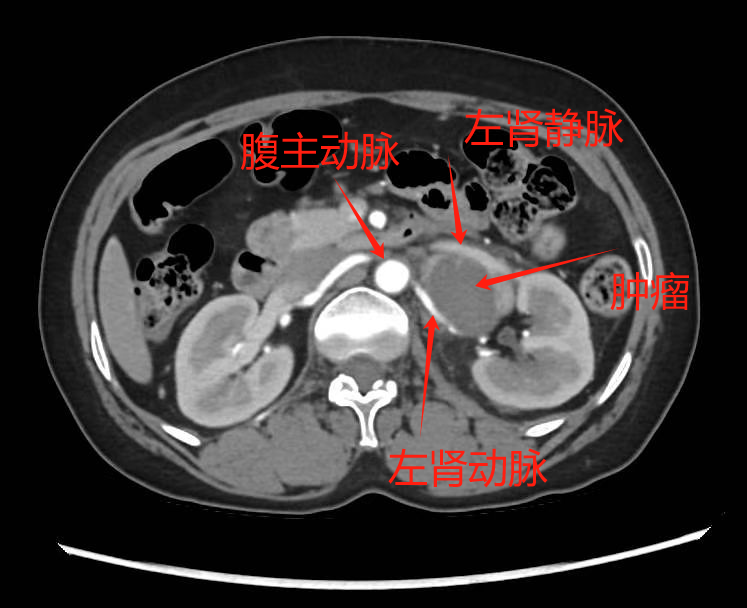

经过充分准备,手术如期进行。术中发现实际情况比预想的更为复杂:肿瘤大小6cm×4cm×4cm,位于左肾门区,紧贴左肾静脉主干、左生殖血管和左肾上腺静脉,并与胰腺、肾上腺高度粘连

肿瘤位置

“手术就像在血管丛林中拆弹,稍有不慎就可能引发大出血。”谢主任描述道。在麻醉团队的精准配合下,手术团队小心翼翼地分离肿瘤与周围组织的粘连,避开重要血管。经过3小时的精细操作,肿瘤被完整切除,左肾得以完好保留,又没损伤胰腺、肾上腺等周围器官,出血量控制在了安全范围内。

泌尿外科谢克基主任团队评估发现:这个4cm的肿瘤位于解剖复杂的左肾门区,影像显示其被多根大血管包绕。“就像在输油管道旁拆除炸弹,”谢主任解释,“术前CT显示肿瘤与血管鞘界限不清,这类患者未经规范术前准备的手术死亡率可达20%-45%,甚至更高。”进一步的检查证实,持续的高血压已经对张女士的心脏造成了损伤,这更增加了手术风险。面对这一复杂病例,医院立即启动了多学科会诊机制。